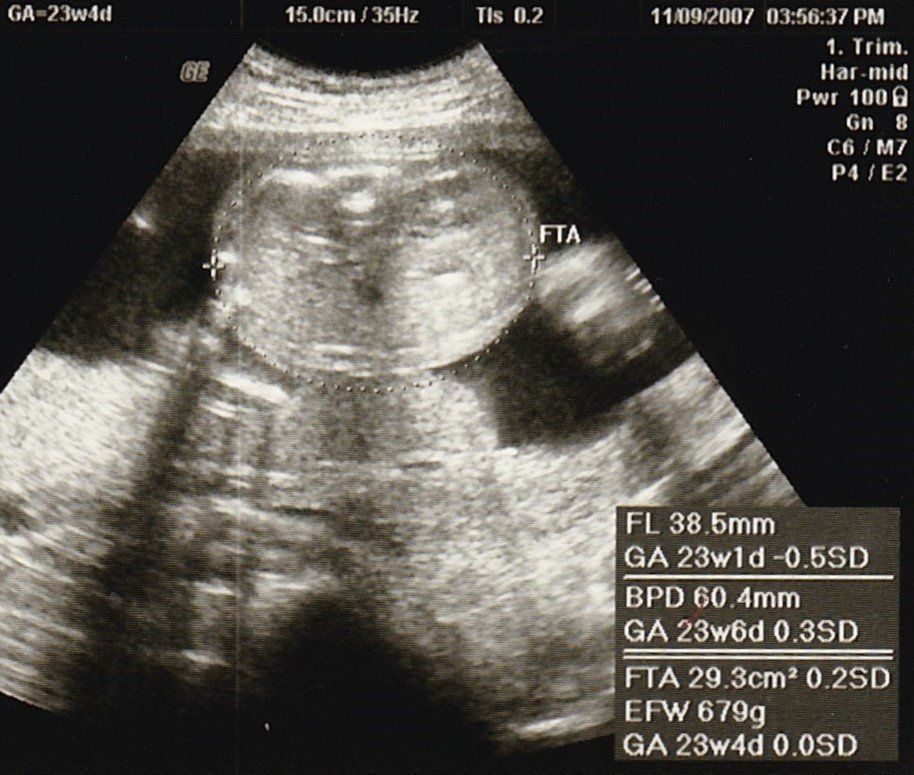

妊娠23週目のエコー写真

推定体重679g。大きくなったためエコー画像に収まらなくなり、胎動もよく感じるようになりました。運動や、母親学級に参加したことで、初めてのママ友ができ、マタニティーライフを満喫。結婚して引っ越してきた土地で、近所に友人もおらず、平日に近所を歩くこともなかったので、毎日がとても新鮮でした。妊娠生活や、地域の情報なども交換でき、有意義な時間がすごせました。ただ、その目的で、お茶やランチをしていたせいか体重はどんどん増えるばかり。